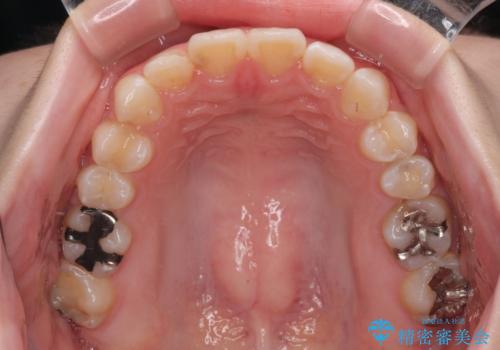

叢生が軽度であったため、僅か半年で装置を除去することができました。